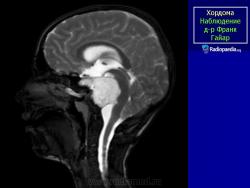

Хордома - медленно растущая злокачественная опухоль, встречающаяся в 1-4 % случаев злокачественных опухолей костей и образующаяся из остатков хорды (спинной струны). Локализация: хордома может развиваться в позвонках, большей частью шейных и грудных, но у половины больных - в крестцово-копчиковом отделе, а также в области турецкого седла, затылочной и верхнечелюстной областей. У мужчин хордома встречается в два раза чаще, чем у женщин. Основная часть больных - лица в возрасте 50- 70 лет. Хордома затылочной области редко превышает несколько сантиметров в диаметре, но при локализации в крестцово-копчиковой области она может стать гигантской (массой до 6,5 кг).

Случай 4: тело позвонка C2